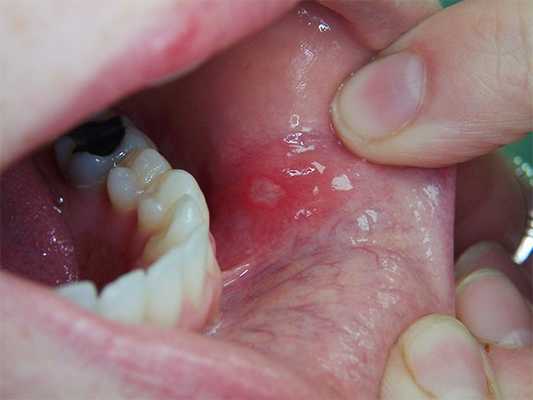

При осмотре (рис. 2) на слизистой оболочке дна полости рта в области премоляров и первого моляра нижней челюсти слева выявляется ограниченный участок эрозии размером 2 ? 5 мм.

Рис. 2. Лейкоплакия слизистой оболочки рта пациента С.